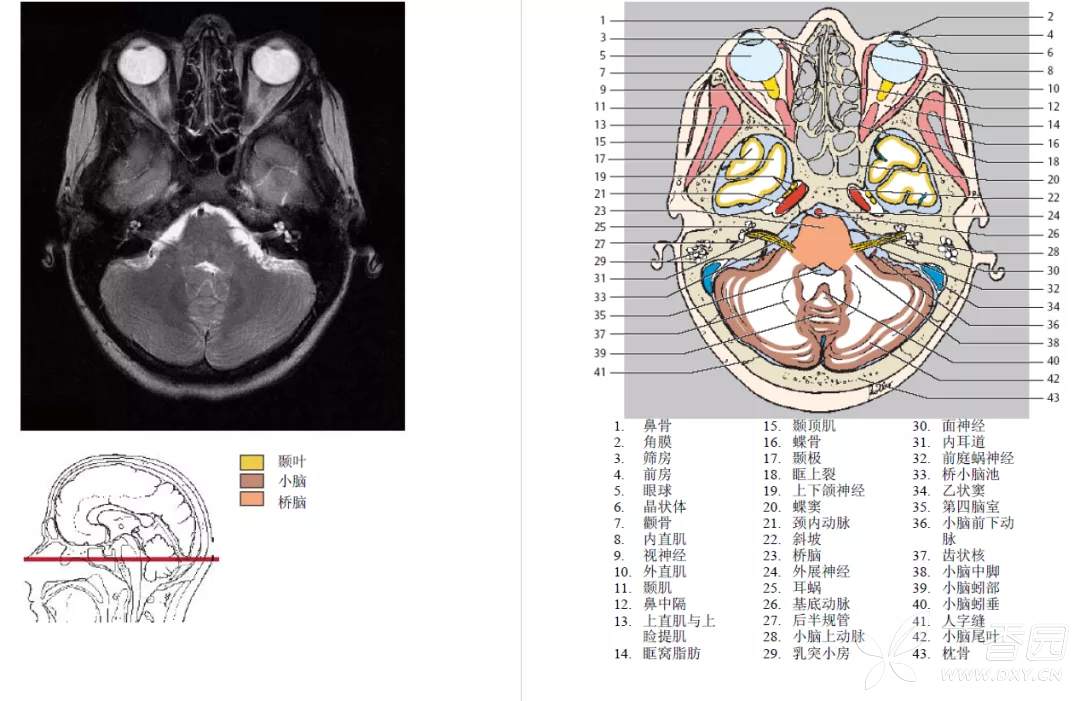

脑桥小脑角池

脑桥小脑角池 cistern of pontocerebellar angle 又名桥池侧突,为桥池向外侧的延续。其前外侧界为颞骨岩部的后内侧壁,后界为小脑中脚和小脑半球,内侧界为脑桥基底部或延髓上外侧部。第四脑室外侧孔开口于此池,面神经和前庭蜗神经经此池入内耳道,小脑下前动脉和迷路动脉也越经此池。

听神经瘤可使脑桥小脑角池内出现肿块影并伴有内耳门、内耳道扩大或形态改变等。